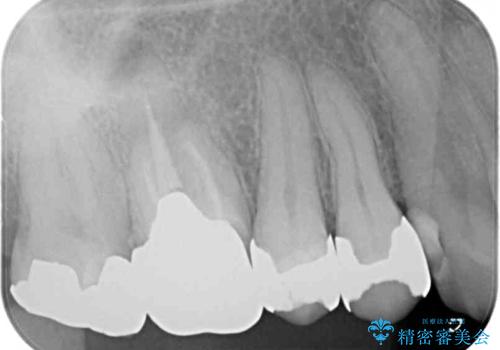

- 右上の小臼歯部に咬んだときに強い痛みを感じるとのことで来院された患者様です。

診査を行った結果、根管治療を行った後にオールセラミッククラウンにて補綴する治療計画となりました。

咬んだときの痛みに加えて夜間のズキズキする痛みもありましたが、1回目の根管治療実施後間もなく咬んだときの痛みがなくなったので、2回目に根管充填を行いました。